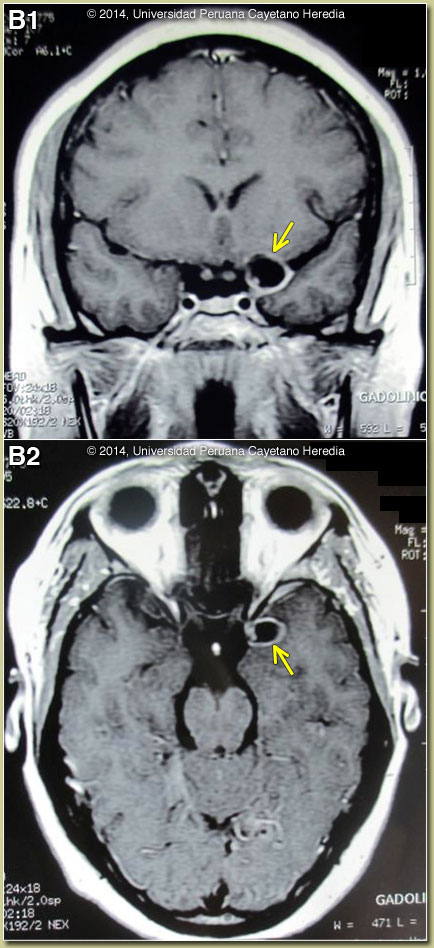

Discussion: This case illustrates the limitations of CT scan alone in fully assessing patients with possible neurocysticercosis. Two CT scans in this case – Image A as well as one done on admission to our hospital (not shown) – were reviewed and were normal. The MRI shown in Image B demonstrates a single fluid-filled cystic lesion in the sub-arachnoid space in the temporo-parietal fissure on both coronal and transverse cuts. The lesion is adjacent to the left side of the optic chiasm. On the periphery of the cyst, a single punctiform structure compatible with the scolex is seen [see